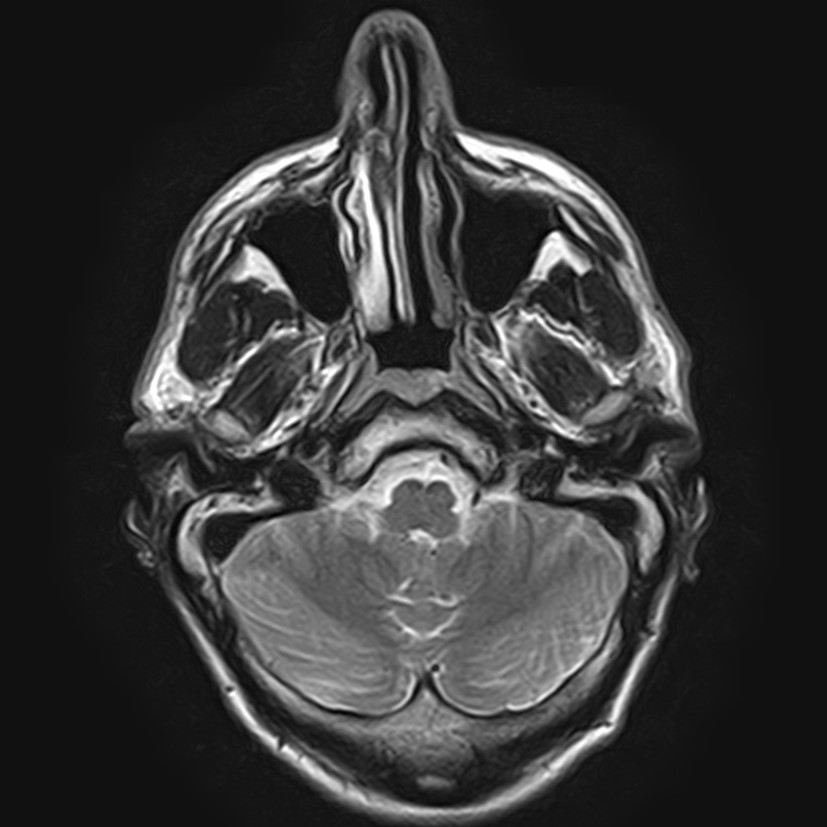

Височно-нижнечелюстной сустав является парным комбинированным суставом и имеет сложное строение. В него входят суставные ямки височной кости, суставные головки нижней челюсти и расположенные между ними хрящевые пластинки – мениски, выполняющие роль амортизаторов.

Чаще всего дисфункция височно-нижнечелюстного сустава обусловлена внутренним повреждением, смещением мениска и суставной головки нижней челюсти. Для определения степени смещения внутрисуставных структур выполняется функциональная проба с проведением МРТ в двух положениях:

• с закрытым ртом;

• с открытым ртом.

Магнитно-резонансная томография является наиболее точным и эффективным методом диагностики поражения височно-нижнечелюстных суставов, так как позволяет получить детальную информацию о состоянии не только костей, но и связочного аппарата, хрящей, менисков, жевательных мышц, окружающих мягких тканей.

При проведении магнитно-резонансной томографии на изображениях визуализируются: височная кость, головка мыщелкового отростка нижней челюсти, суставная щель. Помимо костных структур МРТ позволяет оценить состояние мягких тканей – внутрисуставного диска и связочного аппарата височно-нижнечелюстного сустава, жевательных мышц.

МРТ ВНЧС с капой включает в себя два протокола: с открытым ртом и с закрытым ртом. Данная функциональная проба позволяет проследить степень смещения внутрисуставных анатомических структур и оценить биомеханику движений в суставе.